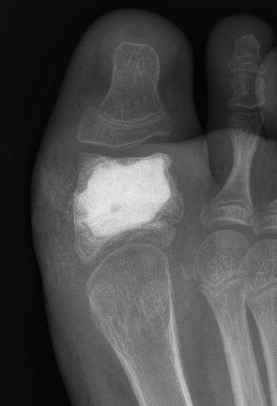

Enchondroma

Single or multiple

www.boneschool.com/enchondroma